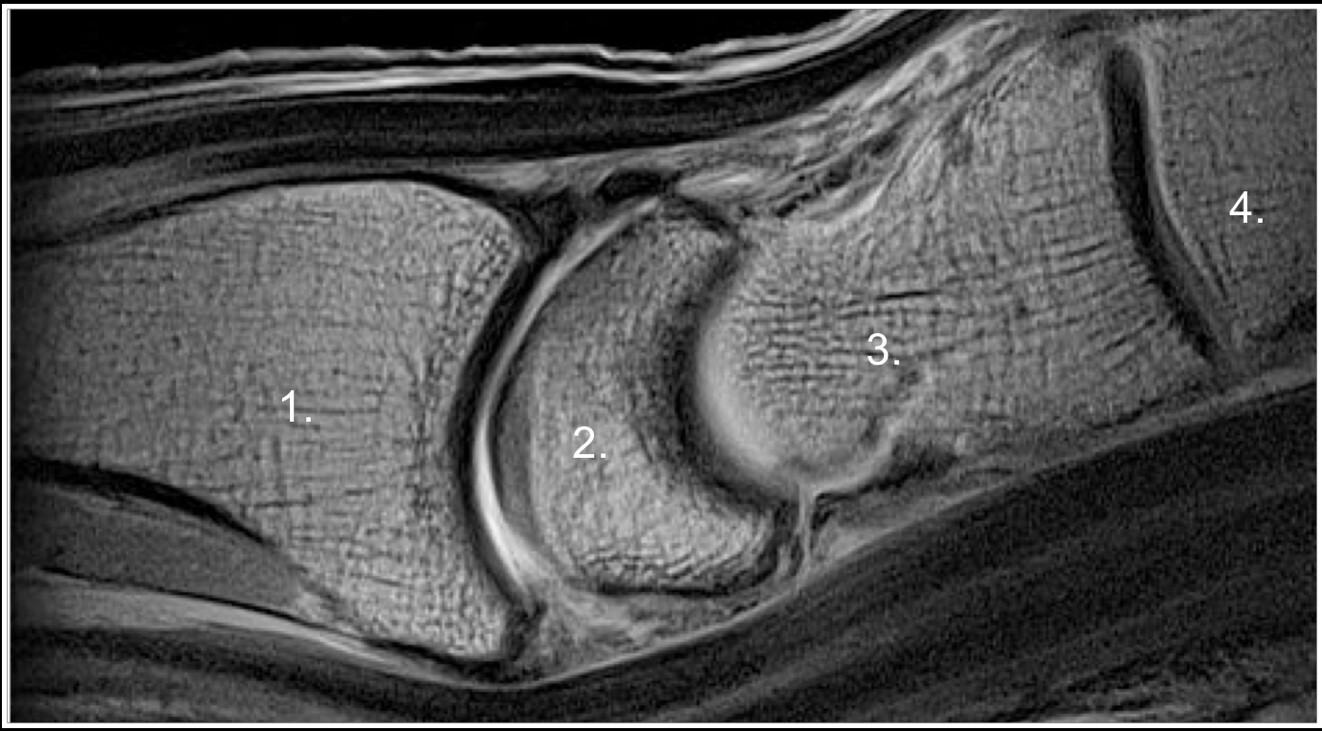

Dorsal Wrist Synovitis MRI Image

Radius

Lunate (moon-shaped)

Capitate (bell-shaped)

3rd Metacarpal